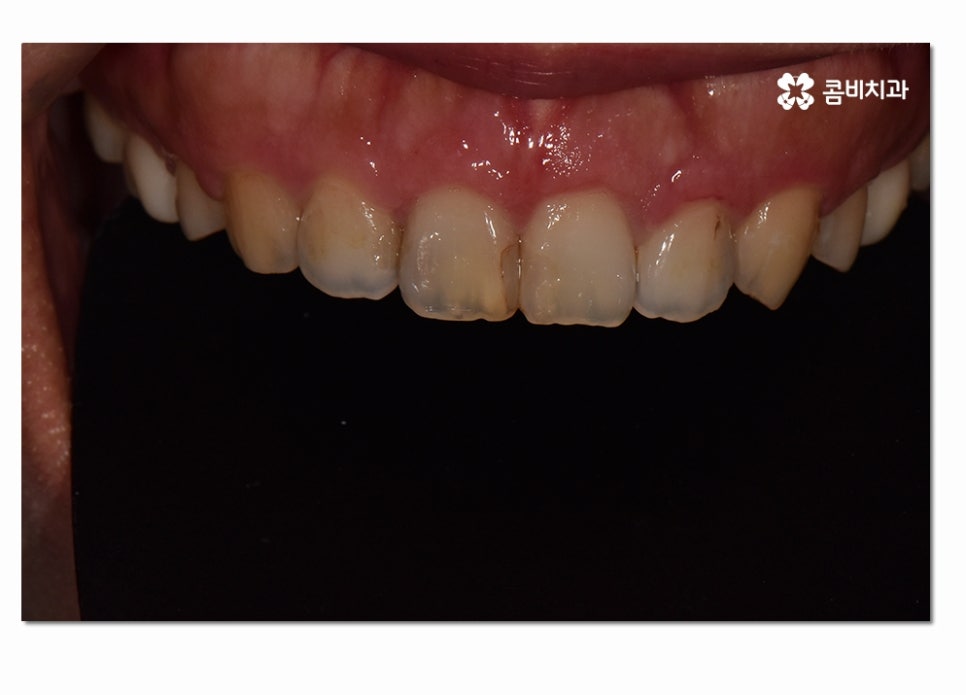

위에 보시는 것처럼 치은절제술 치료가 잘 이뤄지고 잇몸이 다시

건강한 색과 모양으로 회복된 것을 느낄 수 있는데요.

치조골이 파괴되면 치아를 흔들리게 할 뿐 아니라

인접한 치조골의 파괴로 이어져서 여러 치아의 상실로 이어지기도

하며 임플란트를 해야 할 때 뼈이식을 추가적으로 받아야

하는 경우도 많기 때문에 잇몸 상태가 좋지 않다면

꼭 미리미리 치료를 받으시는 것이 자연치아를 잘 보존하는 방법이라고 할 수 있어요.